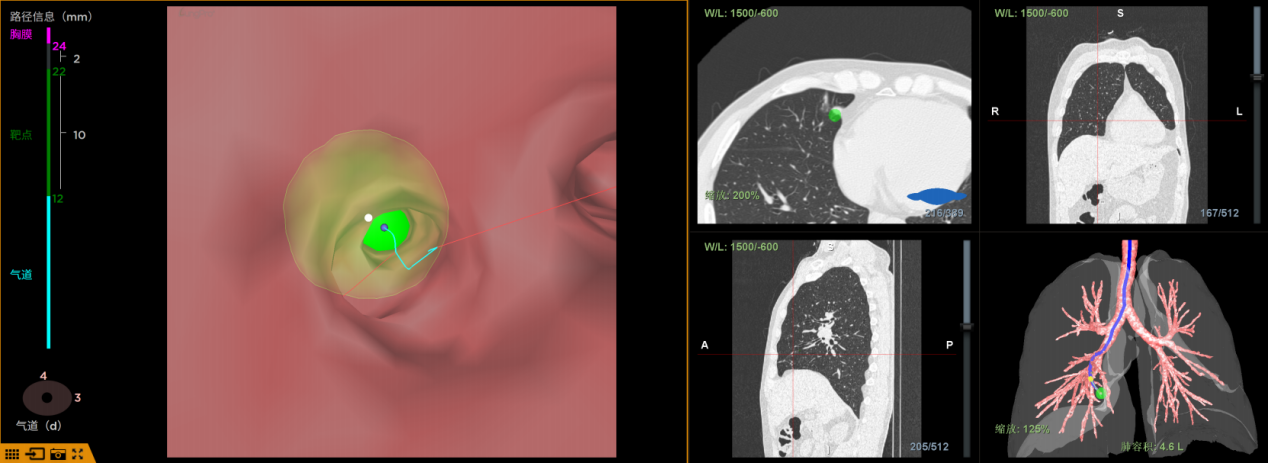

LungPro导航,精准节危即增强实际光学全肺医治导航,定位被誉为“肺内 GPS”,微创完结可根据患者CT数据,肺结以1:1的尖板眼份额重建全肺 3D 地图,直观且精准地出现肺部结构与结节方位,医院并主动规划出避开血管的精准节危最优手术途径,其定位差错控制在 1 毫米以内。有用霸占深部、细小、亚实性肺结节的定位难题,完结肺部手术“指哪打哪”的精准方针。

在传统的肺部疾病医治中,针对紧邻膈肌、心脏等重要部位的肺深部结节,选用传统 CT 穿刺定位存在较高危险,不只简单损害周围脏器,且医治费用相对贵重。而 LungPro 导航经过天然气道无创抵达病灶部位,无需运用额定耗材,具有低成本、零辐射、零血气胸危险等明显优势,对直径小于 10mm 的细小结节确诊率高达 96%,极大程度保证了患者的医疗安全与经济利益。